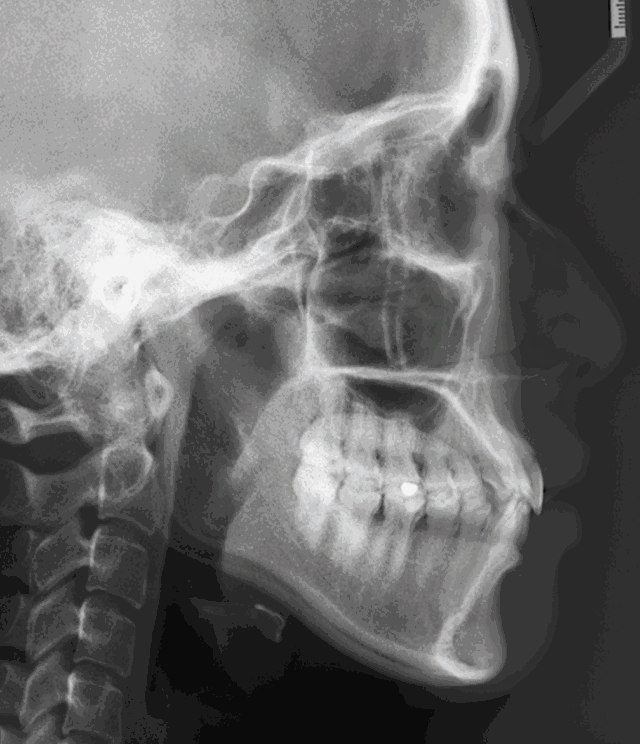

常见的深覆合、深覆盖、牙齿拥挤、反合以及牙缝过大,隐形矫正都可以取得良好的效果。

隐形矫正的程序是怎样的?

在对牙齿排列情况进行过详细的检查评估之后,牙医会取得你的牙齿石膏模型;

根据牙齿石膏模型,通过计算机辅助,建立你的牙齿3D模型,模拟牙齿从原始情况到最终期望效果的正畸过程;

设计一系列隐形矫正牙套。需按顺序每两周更换一副,从而达到缓慢移动牙齿的目的。